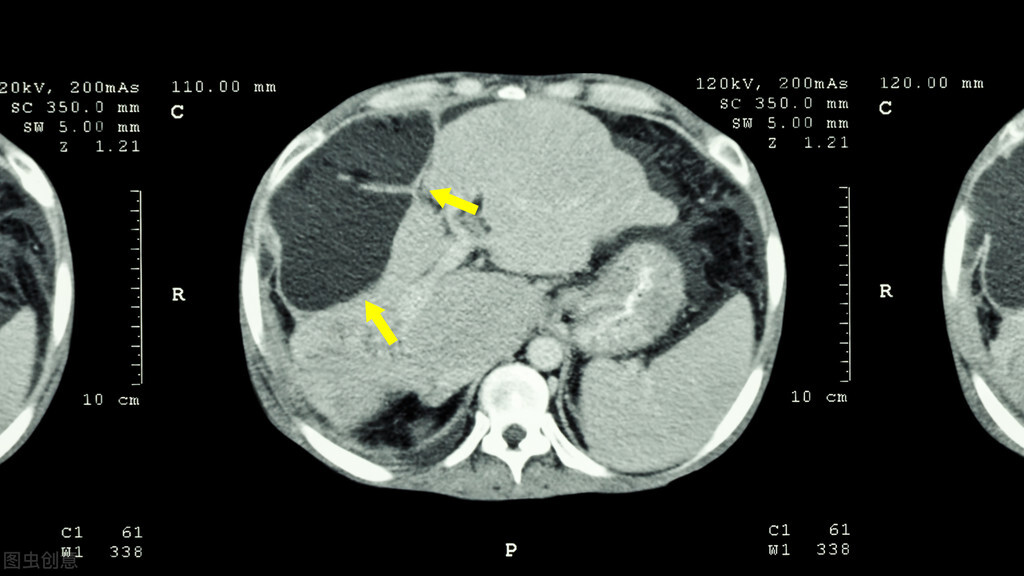

46岁!肝脏右叶就长了个巨大的肿瘤,而且还出现了转移灶;患者及其家属都被这突然的消息吓蒙了,沉默了很久,患者拉着家属就往外走,他不想治疗了……

据了解,患者本人自小就是乙肝病毒携带者,多年来肝功一直都正常,出现症状也就是最近半年的事,他称先是乏力、感觉身上没劲,后来就出现了恶心、呕吐、腹泻等情况,以为吃点药就会好转,但一直没改善,直到今天腹部剧烈疼痛了才过来检查。